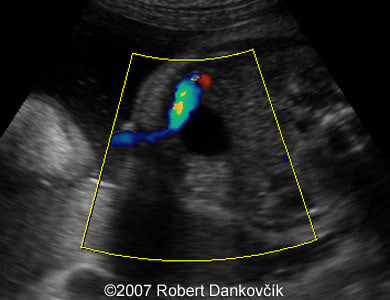

Images 5, 6: Color Doppler (image 5, left) and 2D sonogram showing two vessel umbilical cord.

6

7